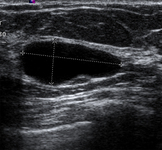

Imagen en ultrasonografía de un quiste simple

Cortesía del Dr. Lane Roland, University of Louisville; utilizada con autorización

Ver esta imagen en el contexto de la/s siguiente/s sección/es: